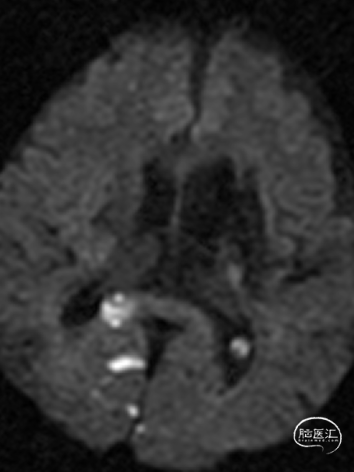

MR:双侧后循环散在急性梗死病灶(双侧小脑半球、双侧枕叶、胼胝体压部、右侧脑桥臂、桥脑右侧部及中脑被盖左侧)。MRA示:双侧椎动脉颅内段及基底动脉明显变窄。